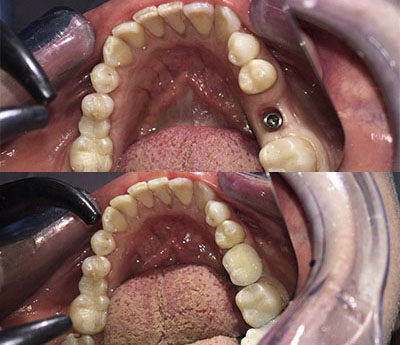

Oltre al ripristino estetico della dentatura, il ponte dentale previene le complicazioni che possono derivare dalla mancanza di un dente. Una volta applicato, completerà il normale processo di masticazione e migliorerà la funzione fonetica.

Il sistema Fast&Fixed è un'alternativa immediata. Questa procedura ti permetterà di ritrovare il tuo sorriso in un unico intervento. Il risultato è immediato e recupererai autostima e fiducia in te stesso.